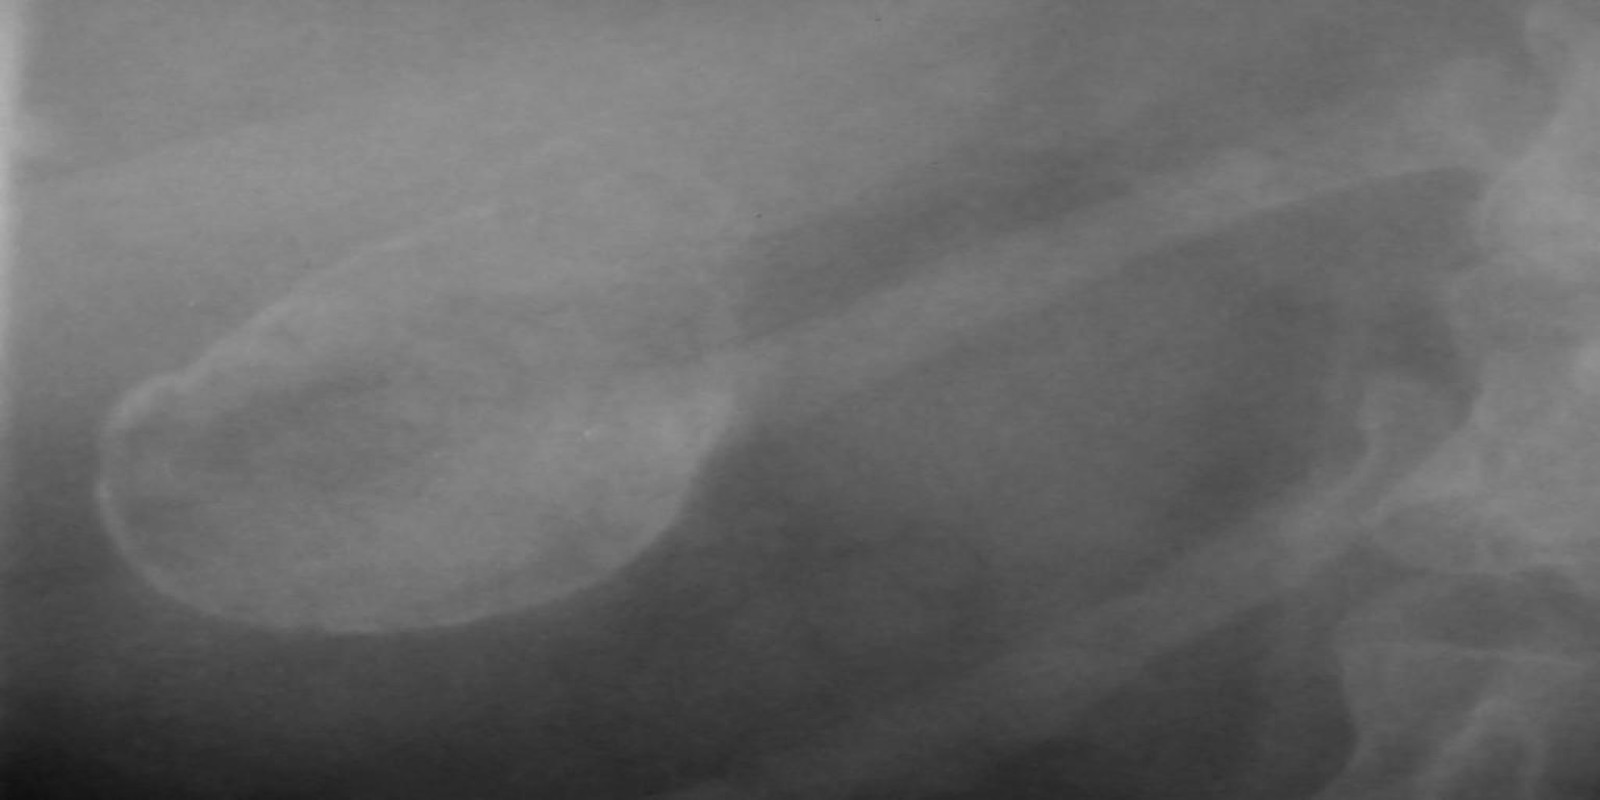

Caso Código 025C de Câncer da Vesícula Biliar

Cod.: 025C